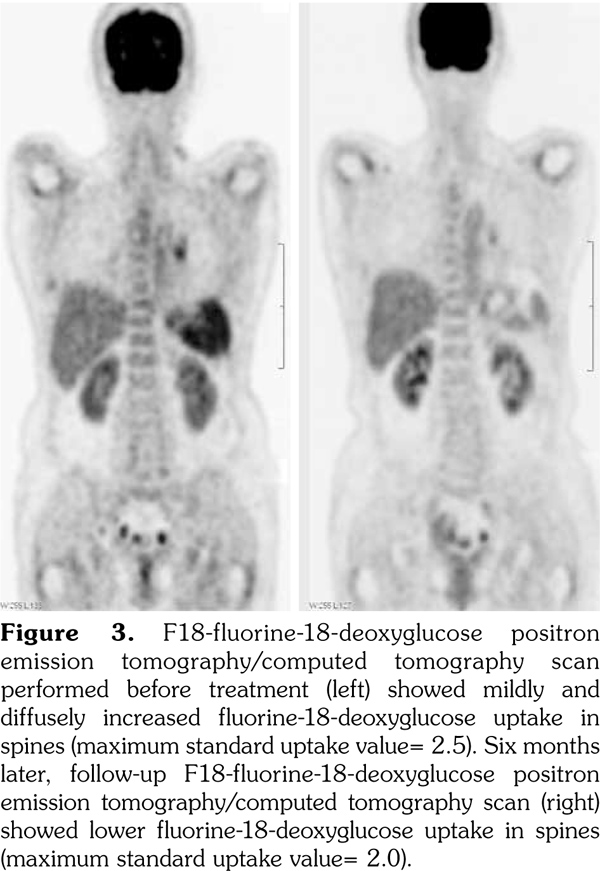

In this case, we were unable to diagnose bone marrow involvement since no bone marrow biopsy was performed. There was mild and diffuse increase of FDG uptake in the bone marrow with a maximum standard uptake value of 2.5 in the spines, which was similar to the FDG uptake in the liver. According to a study by Inoue et al.,(14) a bone marrow F-18 FDG uptake greater than or equal to that of the liver may indicate bone marrow hyperactivity. Therefore, bone marrow involvement could not be ruled out in this case. The PET/CT six months later revealed that the maximum standard uptake value decreased to 2.0 in the spines and was less than that in the liver (Figure 3).